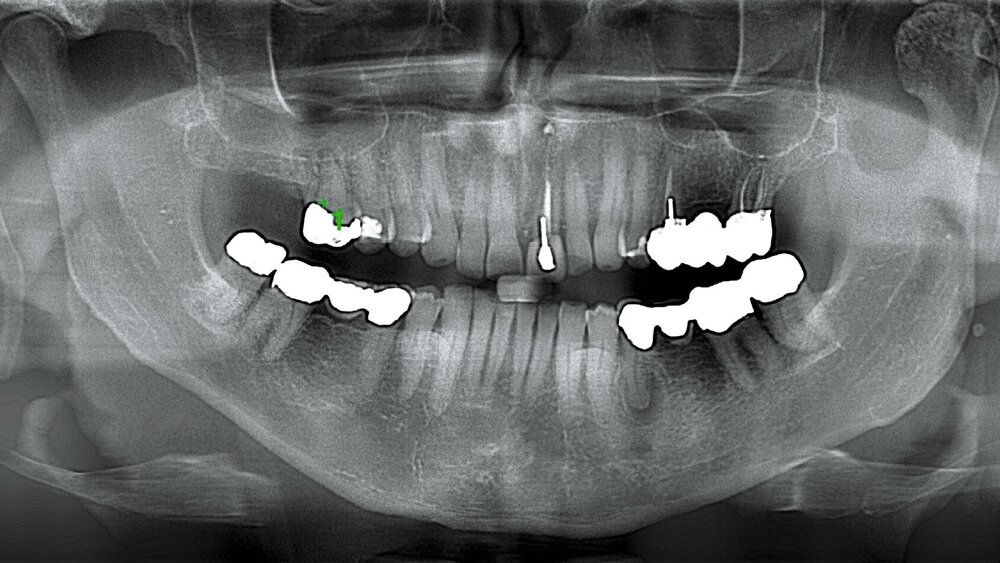

Ein 59-jähriger Patient stellte sich aufgrund eines radiologischen Zufallsbefunds in einer Panoramaschichtaufnahme in der Klinik und Poliklinik für Mund-, Kiefer- und Gesichtschirurgie der Universitätsmedizin Mainz vor. In der Bildgebung zeigten sich ein gegenüber der Gegenseite deutlich aufgetriebener Condylus mit streifigen Verdichtungen und ein freier Gelenkkörper (Abbildung 1).

Zur Diagnose eines Osteochondroms wird zunächst ein Orthopantomogramm angefertigt, in dem sich das tumoröse Wachstum am Condylus als knöcherne Anlagerung erkennen lässt (Abbildung 1). Liegt der Tumor jedoch medial am Condylus, bleibt er in einer zweidimensionalen Aufnahme möglicherweise verborgen, so dass ergänzende Verfahren wie die Digitale Volumentomografie oder die Computertomografie notwendig sind [Reich und Neff, 2022; Gupta et al., 2020].